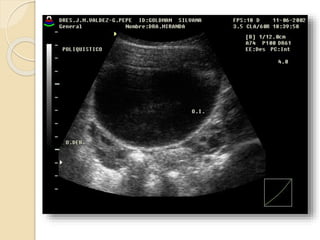

Poliquistosis Ovárica:

Se describe este síndrome como cambios

escleroquísticos en el ovario, mas

amenorrea, infertilidad e hirsutismo.

Ecográficamente vamos a ver

agrandamiento de ambos ovarios con

quistes subcorticales de menos de 1cm.,

mas incremento de las dimensiones del

estroma y fibrosis subcapsular.